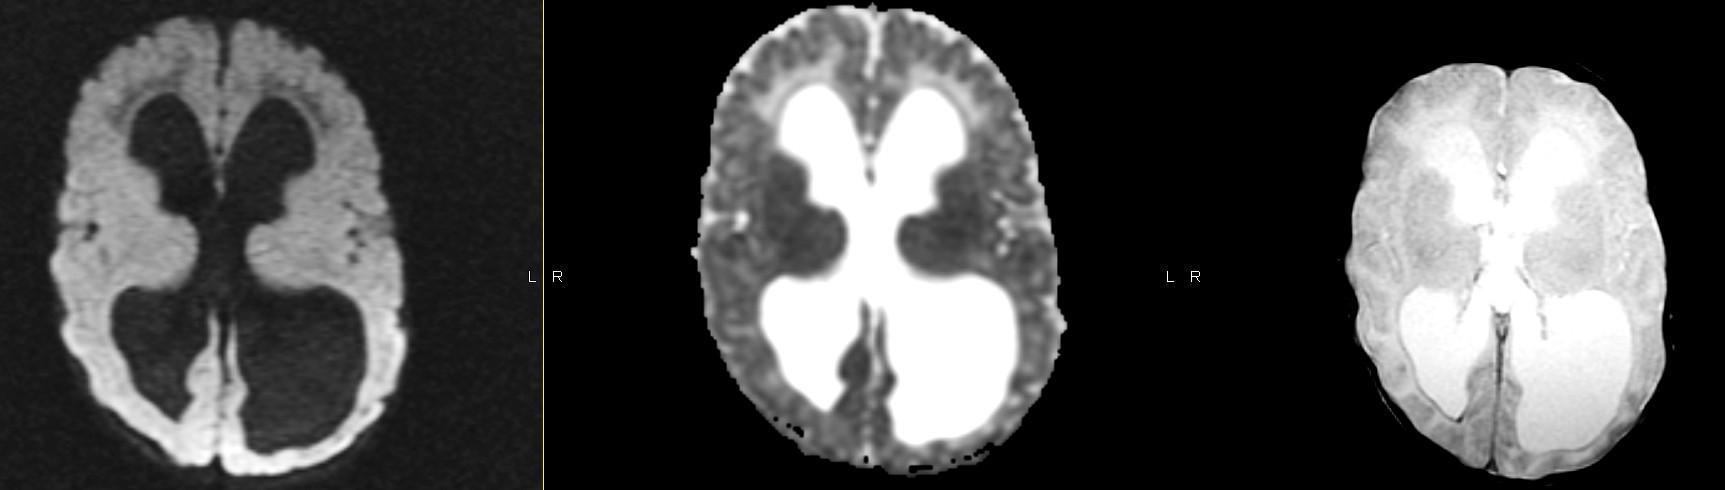

Ice the Cake: Use remaining sequences (GRE, DWI, contrast) to refine your diagnosis.

Cerebellar dysgenesis

Fused hemispheres, absent or hypoplastic vermis, and superior cerebellar peduncles

Needs to have fusion of the dentate nuclei

Assn: hydrocephalus, limbic anomalies, cortical malformations, absent septum pellucidum, multiples suture synostosis